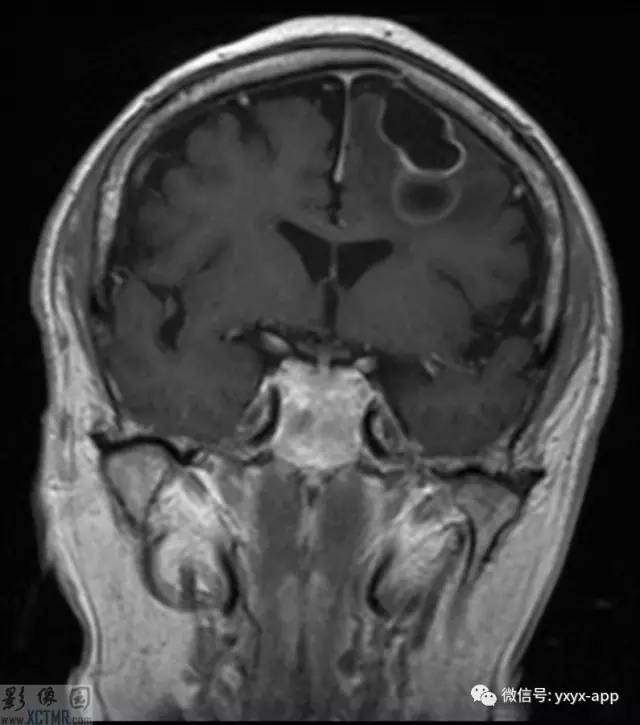

CT:左侧额叶一囊性肿块伴水肿。MRI:轴位T1WI和T2WI显示左侧额叶一囊性肿块伴周围脑实质显著水肿,但无明显占位效应。T1WI增强图显示病变为分叶环形囊状肿块伴周围脑实质水肿,囊壁环形强化,囊内及周围水肿区无强化。

影像学表现取决于感染的位置以及感染的阶段。此病例在胶状水泡阶段,寄生虫的死亡引起明显的炎性反应。影像学表现包括:围绕囊性病变的血管源性水肿;增强后环状增强;T1WI胶状囊性病变周围为低信号;有时可见T1WI头节高信号影。